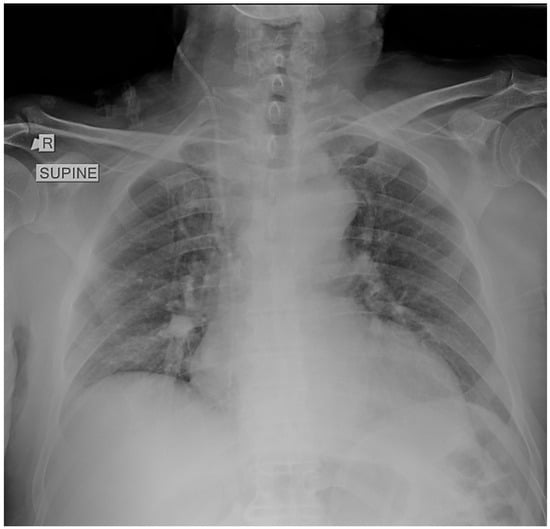

2. Case Presentation